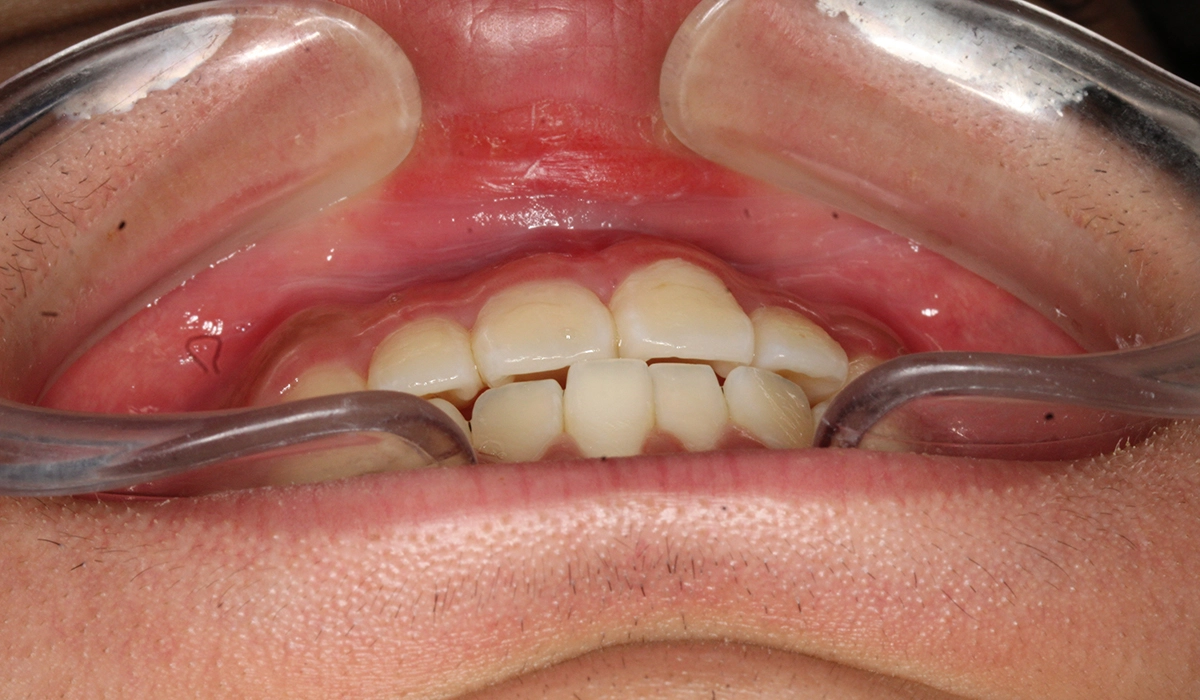

術前:前歯部あおり